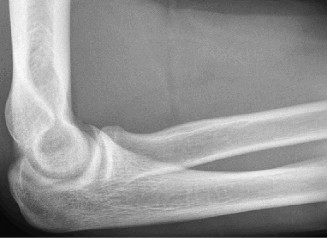

Examination reveals deformity about the elbow with no open lesions or skin tenting. He has a palpable radial and ulnar pulse and is neurologically intact. His images are shown (Figs. 2–85 to 2–88).

Figure 2–85

Figure 2–86

Figure 2–87

Figure 2–88

What is the diagnosis and direction of displacement?

- Monteggia fracture dislocation, posterolateral displacement of the forearm about the humerus

- Simple elbow dislocation, posterolateral displacement of the forearm about the humerus

- Transolecranon complex elbow dislocation

- Simple elbow dislocation, posteromedial displacement of the forearm about the humerus

Discussion

The correct answer is (B). This is the most common type of elbow dislocation, and often does not cause any osseous injury. Posterolateral and posteromedial dislocation account for approximately 90% of dislocations. Adequate pre- and postreduction films are necessary to evaluate for fracture, which would change the classification to a complex injury.